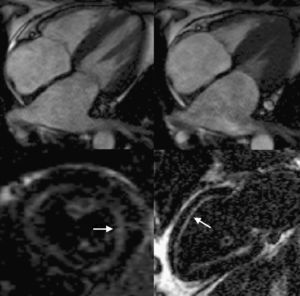

Resonancia magnéticaLa resonancia magnética (RM) permite una caracterización morfológica excelente (especialmente útil cuando hay limitaciones técnicas en las imágenes ecocardiográficas46), con alta reproducibilidad y la ventaja añadida de permitir el estudio mediante la técnica de realce tardío con gadolinio (Figura 4). El depósito de amiloide afecta específicamente a la cinética de distribución del gadolinio entre la sangre y el miocardio. Así, tras la administración de gadolinio se encuentra un mayor acortamiento del T1 subendocárdico y de la diferencia entre la señal en T1 de subendocardio y de sangre. Esta menor diferencia entre el subendocardio y la sangre se considera que refleja la rápida captación de gadolinio por los depósitos amiloides del miocardio y su desaparición rápida de la sangre. El patrón de captación de gadolinio en los pacientes con amiloidosis cardiaca se describió inicialmente como subendocárdico y general (sin afección circunscrita a un territorio coronario, como ocurre en la cardiopatía isquémica)47. Posteriormente se ha comprobado que el patrón de captación de gadolinio también puede ser parcheado localizado o transmural48, 49 y que incluso existen pacientes que, pese a presentar depósitos cardiacos de amiloide, no muestran captación alguna de gadolinio48, 49, 50. Cabe destacar, además, que la selección del tiempo de inversión T1 puede ser especialmente difícil en algunos casos y que, pese a emplear múltiples secuencias T1, no se logre anular apropiadamente la señal miocárdica, lo que impide determinar el patrón de captación de gadolinio del miocardio49. Algunos trabajos han relacionado la existencia de un patrón de captación general y subendocárdico con fases más avanzadas de la enfermedad49. De hecho, aunque no está establecido por completo el papel diagnóstico de la RM, la coexistencia de este patrón de captación «típico» junto con la demostración de amiloide en otro órgano puede ya interpretarse como sinónimo de afección cardiaca amiloidea y, por lo tanto, se puede evitar la biopsia cardiaca51, 52. Desgraciadamente, todavía desconocemos qué papel puede tener la RM en el diagnóstico en fases precoces de la enfermedad49, 51. En cuanto al papel pronóstico de la RM, no parece que la presencia y la extensión de los depósitos de gadolinio tengan influencia en la evolución de estos pacientes50, 53, 54, pero son necesarios trabajos más amplios, ya que se ha señalado que otras técnicas, como la cartografía T1, podrían caracterizar mejor la cantidad de amiloide intersticial y ofrecer importante información pronóstica54.

Figura 4. Resonancia magnética de 2 pacientes con amiloidosis. Imágenes superiores: planos de cine de cuatro cámaras en diástole (izquierda) y sístole (derecha). Obsérvese la importante hipertrofia ventricular con pobre contracción longitudinal y la gran dilatación biauricular. Imágenes inferiores: tras administración de gadolinio eje corto (izquierda) y apical de dos cámaras (derecha), que muestran captación de contraste a nivel subendocárdico (flechas). Cortesía del Dr. J. Moon, The Heart Hospital, Londres, Reino Unido.